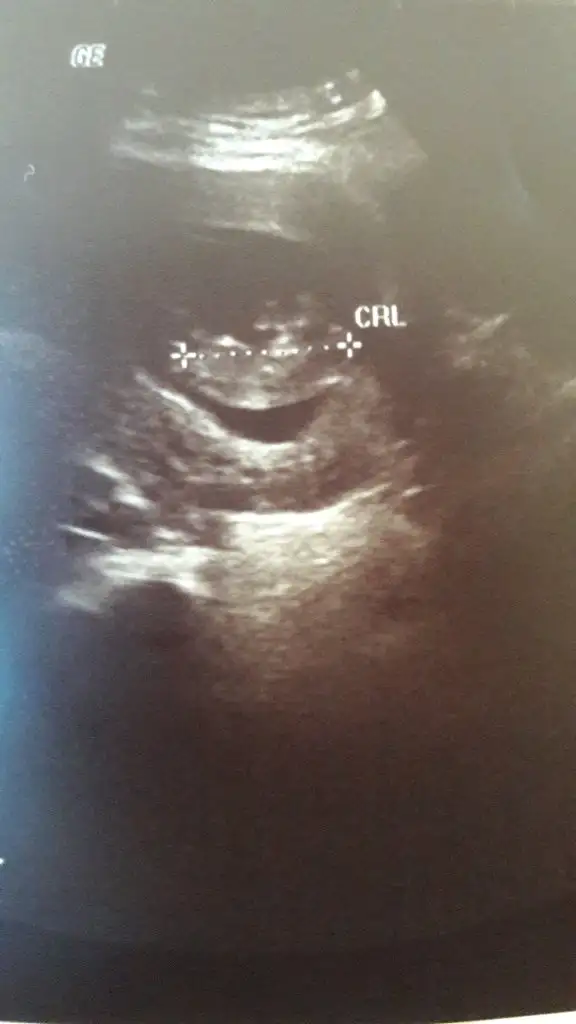

Ikra meyra Ikra meyra mrblar 13 haftalık usg attım kız demiştin canım 14+3 karından bunu da Degerlndirr msn

Eklentiler

• IMG_20210325_114624.webp

IMG_20210325_114624.webp

11,4 KB · Görüntüleme: 60

• IMG_20210325_114547.webp

IMG_20210325_114547.webp

14,1 KB · Görüntüleme: 54